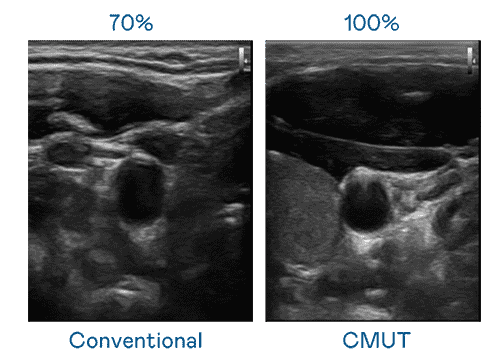

CMUT 技术是一种用电容式微机电元件来产生超音波讯号的技术。。与传统 PZT 压电式技术相比,,,CMUT 频宽增加 30%,,更宽频的超音波讯号让影像解析度大幅提升,,,是实现高影像品质医疗超音波扫描、、、、促进精准医疗发展的关键技术。。。

大频宽带来超清晰影像

超音波影像的解析度高低,,,,首先取决于探头能发出的讯号频宽。。。。财神娱乐 CMUT 可提供高清晰的超音波讯号,,提供高频宽、、高灵敏度、、、、影像纹理细节更高的超音波影像,,协助医护人员缩短影像判读时间及利用精准的医疗影像进行诊断。。。